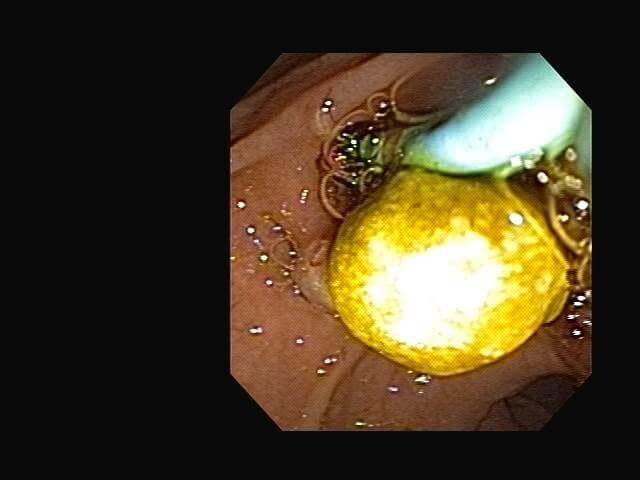

⚕ Endoscopia de alta definición

⚕ Extracción de cálculos biliares